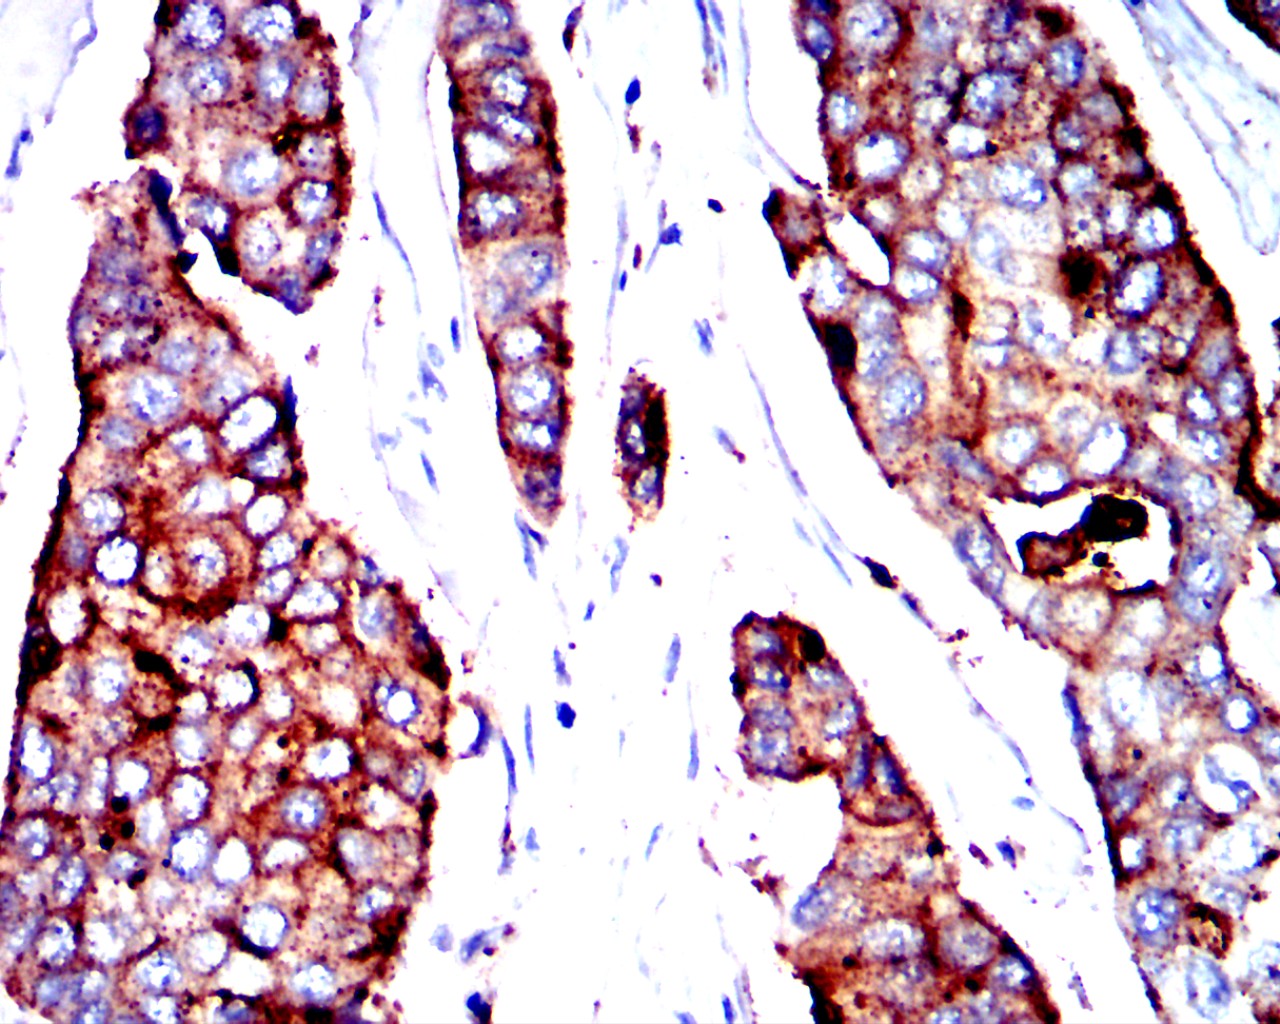

Immunohistochemical analysis of paraffin-embedded human colon cancer tissues using CEACAM5 mouse mAb with DAB staining.

应用详情:IHC:1/200-1/400

CEACAM5 Mouse mAb

别名:CEA;CD66e

计算分子量:76.8kDa